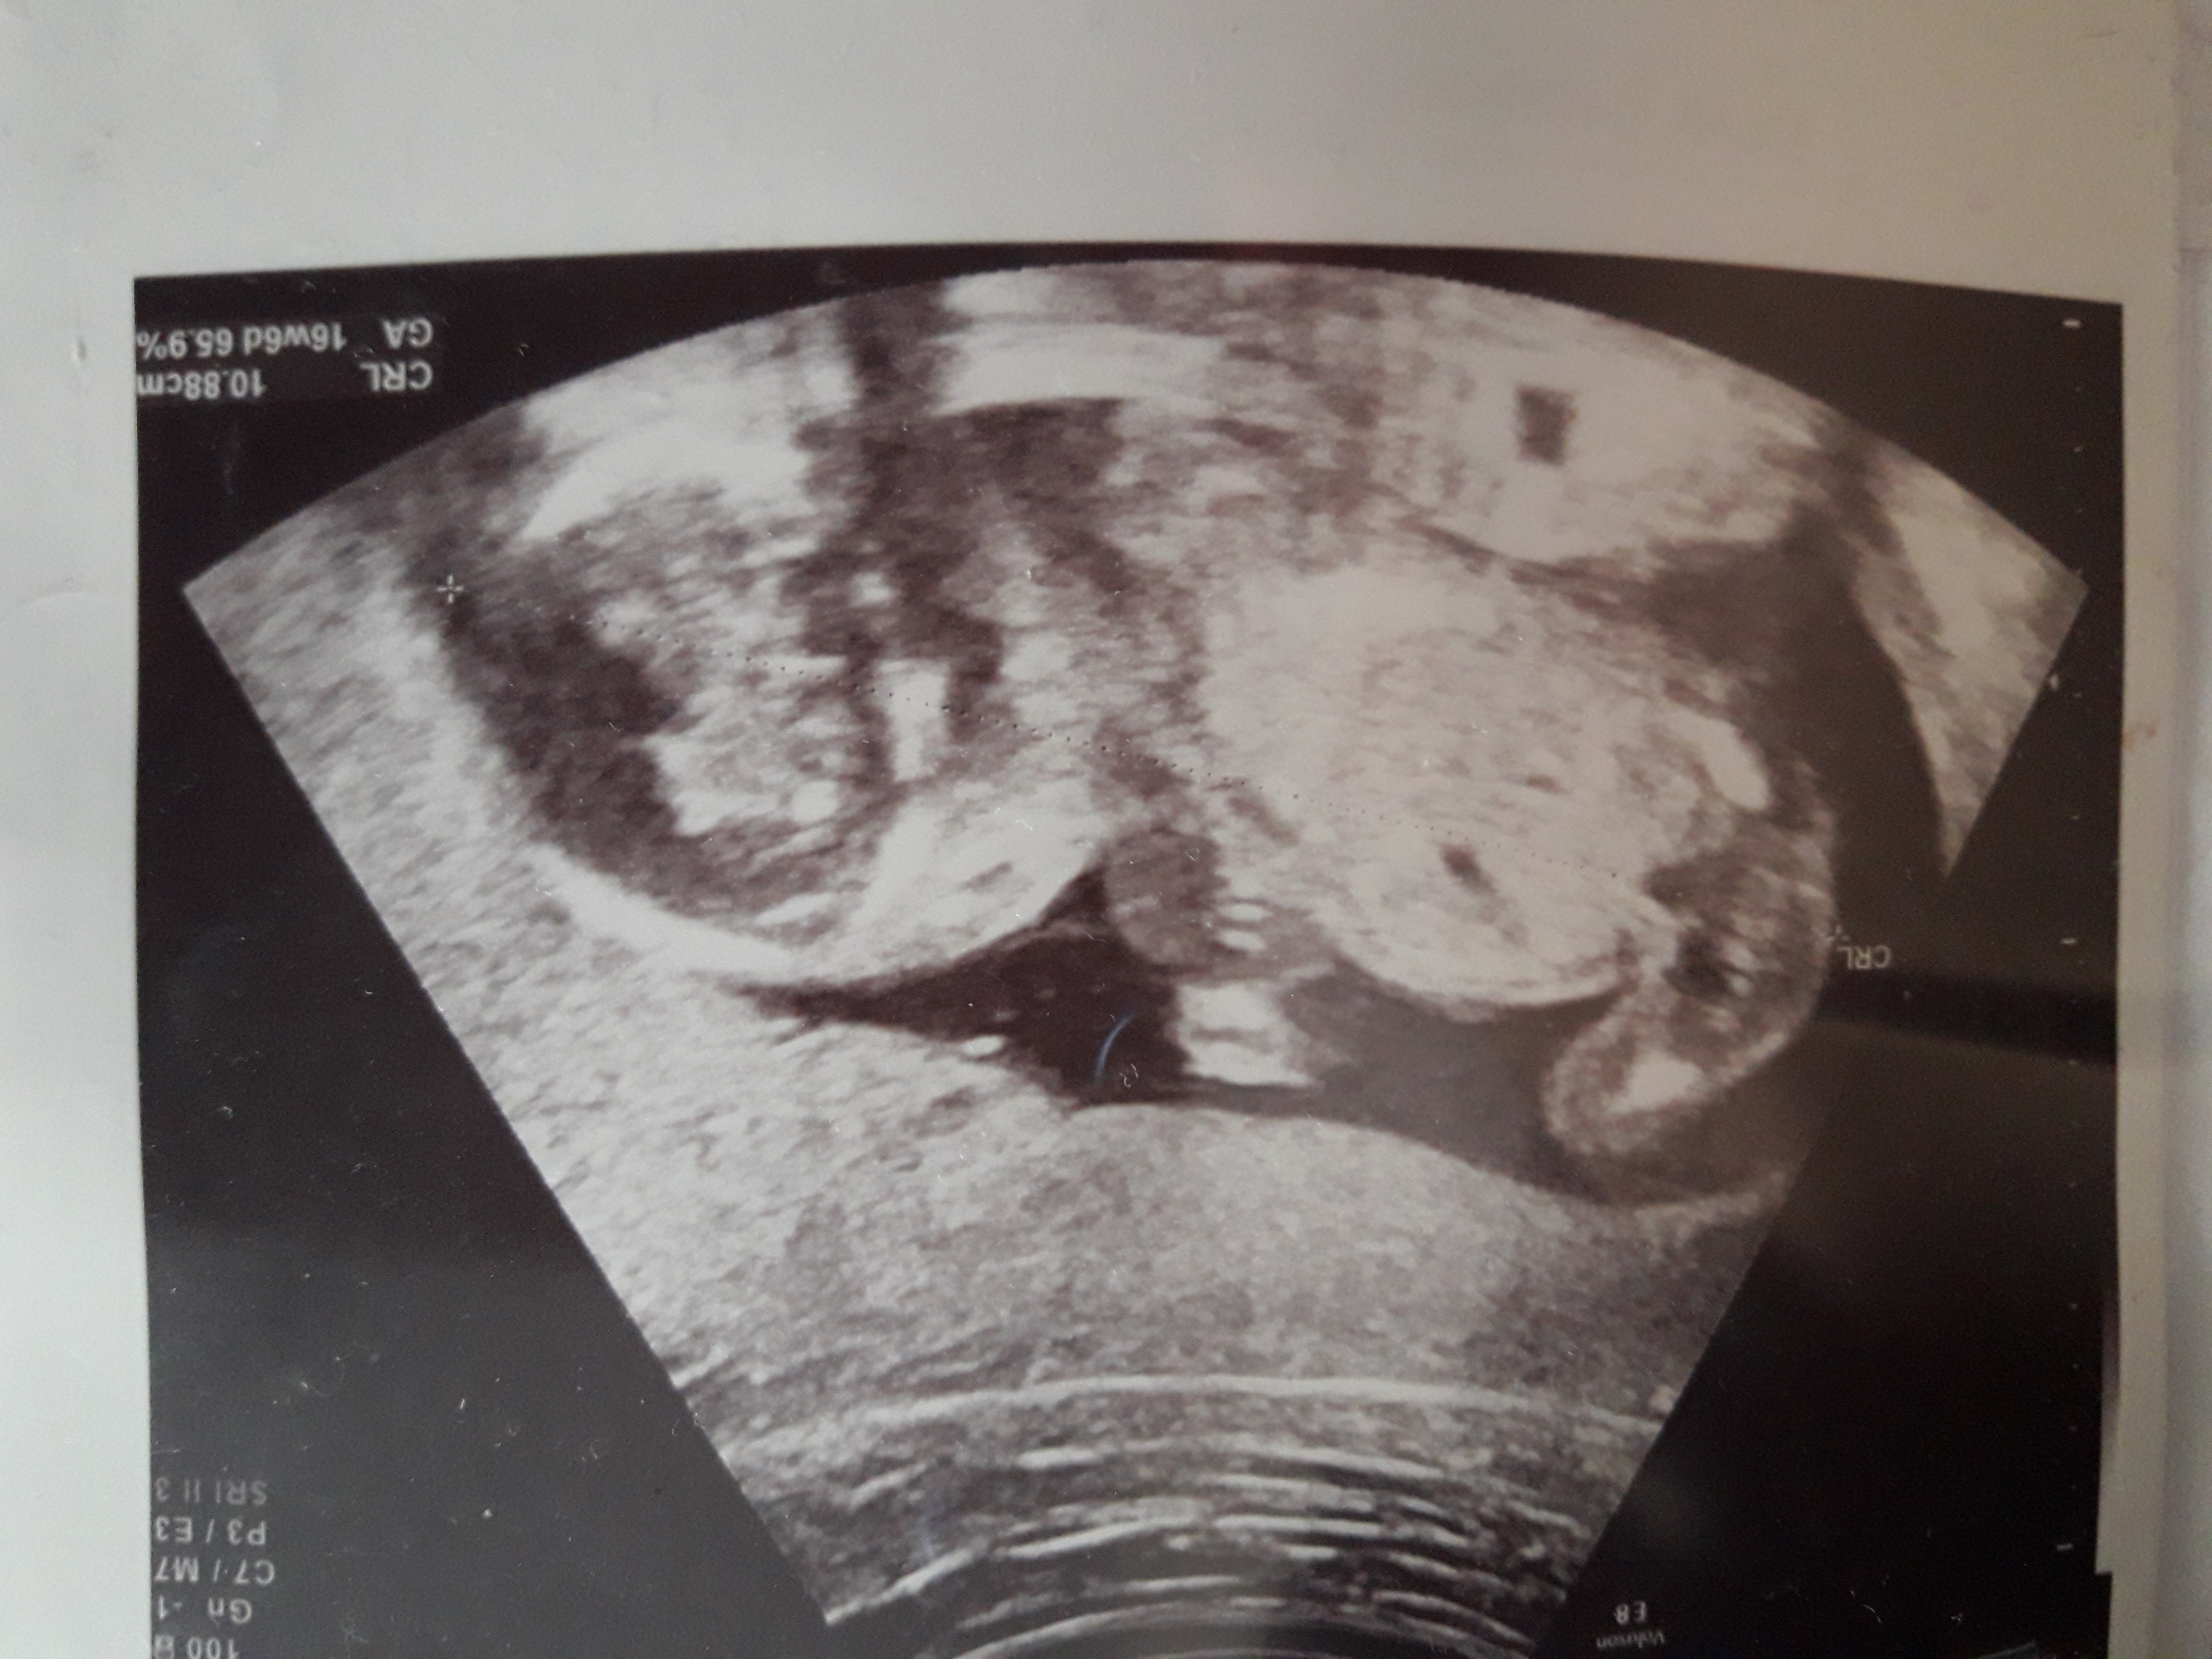

Dziewczyny mała zagadka. Jaka to płeć?

Screenshot_20180723_205057.jpg